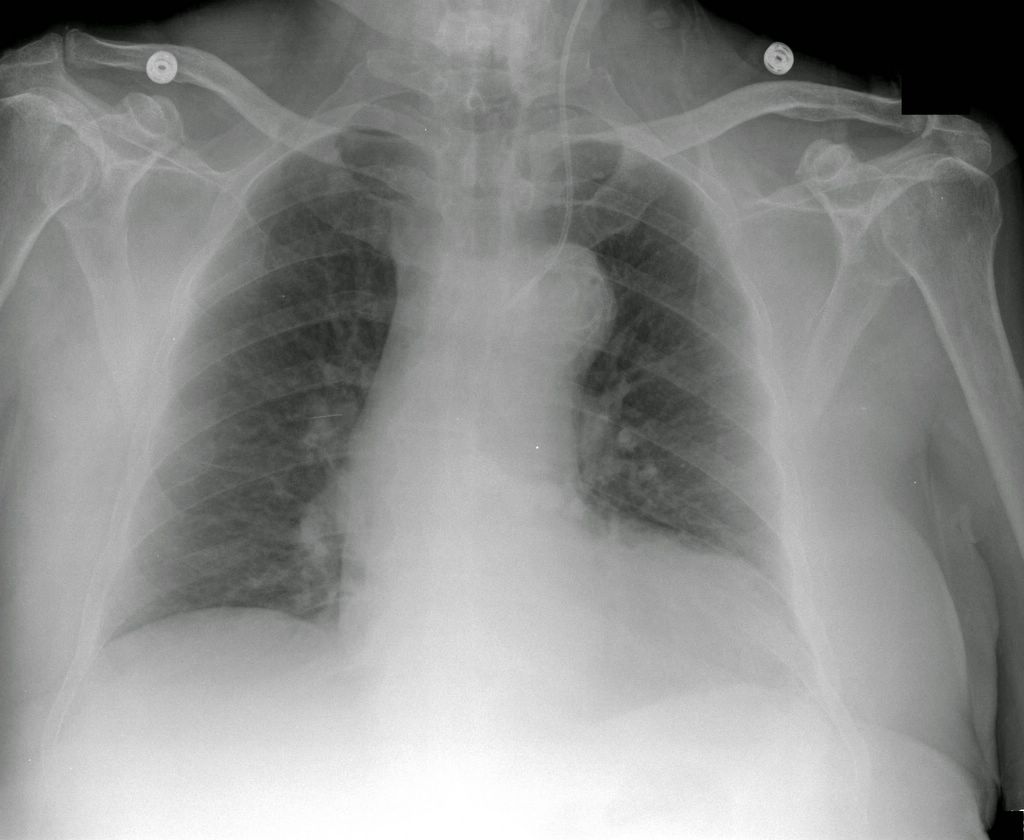

Вентрикуло-перитонеальный шунт: Показания и применение

Раздел: Фотоальбом решений